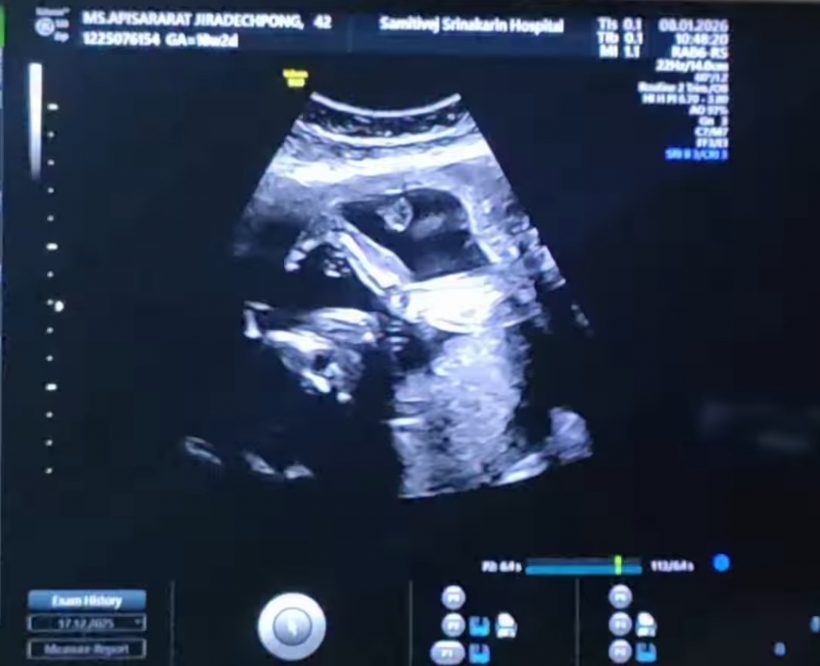

ล่าสุด ลีซอ โพสต์อินสตราแกรม @leesawls14 เผยโมเมนต์อัลตร้าซาวด์ลูกน้อยในครรภ์ภรรยา พร้อมแคปชั่นระบุว่า "รอวันพบกันนะลูกนะ #18w2d #LFbaby"